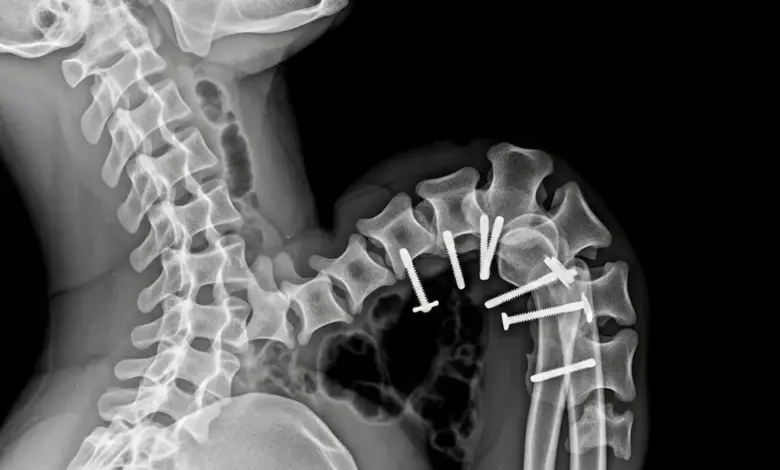

A cirurgia é considerada quando há instabilidade clara, deformidade que progride, dor refratária bem documentada, compressão neurológica ou desequilíbrio do tronco que compromete a função.

As técnicas variam conforme o caso: estabilização com instrumentação, correção do alinhamento e, quando necessário, descompressão de estruturas neurais.

O objetivo é restaurar a estabilidade, melhorar a mecânica e proteger a medula e raízes nervosas.